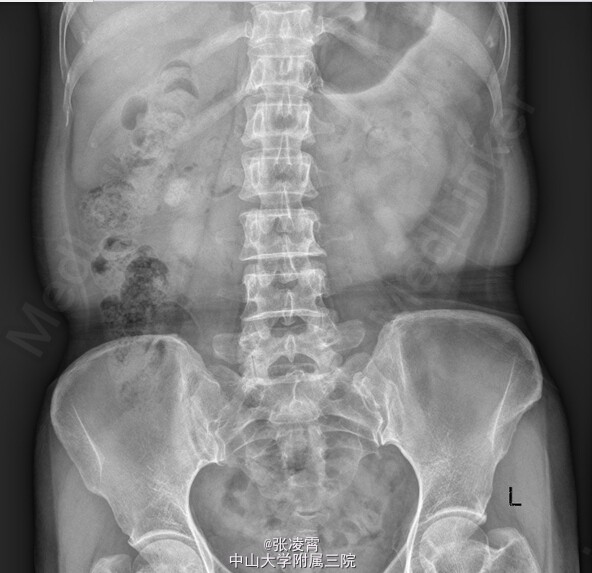

查体:双侧肾区叩击痛(+)。 血常规:白细胞 12.03 ×109 /L;中性粒百分比0.758 尿常规:白细胞 1647.3个/L;红细胞 1135.4个/L 大便常规,凝血四项,生化全套,术前八项等未见明异异常。 KUB示:右肾结石,左侧输尿管下段结石。 CT提示:右肾结石并右肾积水,左侧输尿管下段结石并输尿管扩张。 胸片,心电图大致正常。